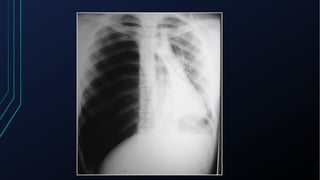

Pneumotórax

• Hipertensivo

• Pressão pleural ultrapassa a atmosférica, resultando em redução do retorno

venoso e do débito cardíaco -> paciente evolui com sinais de hipoxemia e de

comprometimento hemodinâmico

• Decorre de aprisionamento progressivo de ar no espaço pleural, resultado

de um mecanismo valvular que favorece a entrada de ar na inspiração, mas

dificulta sua saída na expiração